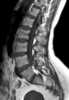

Myelophthisic marrow replacement

Myelophthisic anemia (or myelophthisis) is a severe type of anemia found in some people with diseases that affect the bone marrow. Myelophthisis refers to the displacement of hemopoietic bone-marrow tissue by fibrosis, tumors, or granulomas. [Source: Wikipedia ]